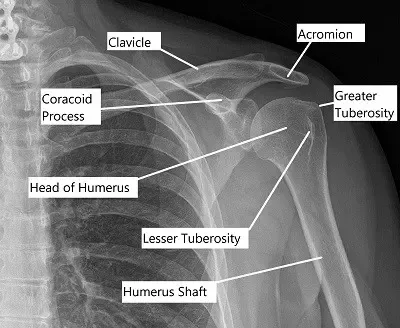

Vista anteroposterior del hombro izquierdo.